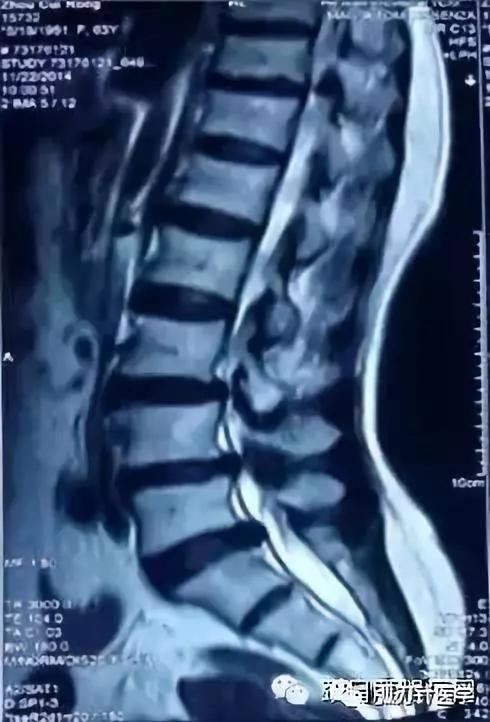

周某,60岁,林州人,腰部酸痛伴左下肢放射性疼痛5年,间断性遇劳后复发,在当地医院给予“拔罐、针灸、膏药”治疗后稍缓解,逐年呈加重趋势。2月前劳累后腰痛伴左下肢放射性麻木疼痛症状加重,间歇性跛行(走很短距离的路程,就会出现左下肢酸痛麻木无力,以至跛行,但蹲下或坐位休息片刻后症状马上消失),在当地多家医院检查后诊断为“腰椎管狭窄症”,是由腰椎间盘突出造成的,均建议手术治疗。患者因惧怕手术,一直坚持保守治疗,效果不佳,间歇性跛行也渐渐加重(走50米左右就下肢麻木不能忍受)。当地有大夫告诉她:“要想不开刀,可以找王学昌教授试试,可能他有办法。”

腰椎管狭窄的影像学改变

CT:诊断符合率96% —100%,正常CT椎管形态为三角形或球形,狭窄的可显示为三叶草、牛角、猫耳形。Korkard测量侧窝神经根管矢径大于5mm 为正常,4 mm 为临界.小于 3mm 为狭窄。椎管与椎体矢状径比值在椎弓板上切迹层面小于0.45 ,在椎间盘层面小于0.35可以确诊,硬膜囊与椎管矢状径比值如低于0.6 以下可以确认。近年来又有CT计算机图形计算椎管横截面积CSAC自L1-S1,逐渐加大,硬膜囊横截面积(CSADS)自L1-S1,逐渐减小,来评估椎管狭窄。 MRI :它不能提供精确的定位与清晰的图像,诊断符合率占 82%一 91%,但在鉴别诊断方面可显示椎管。